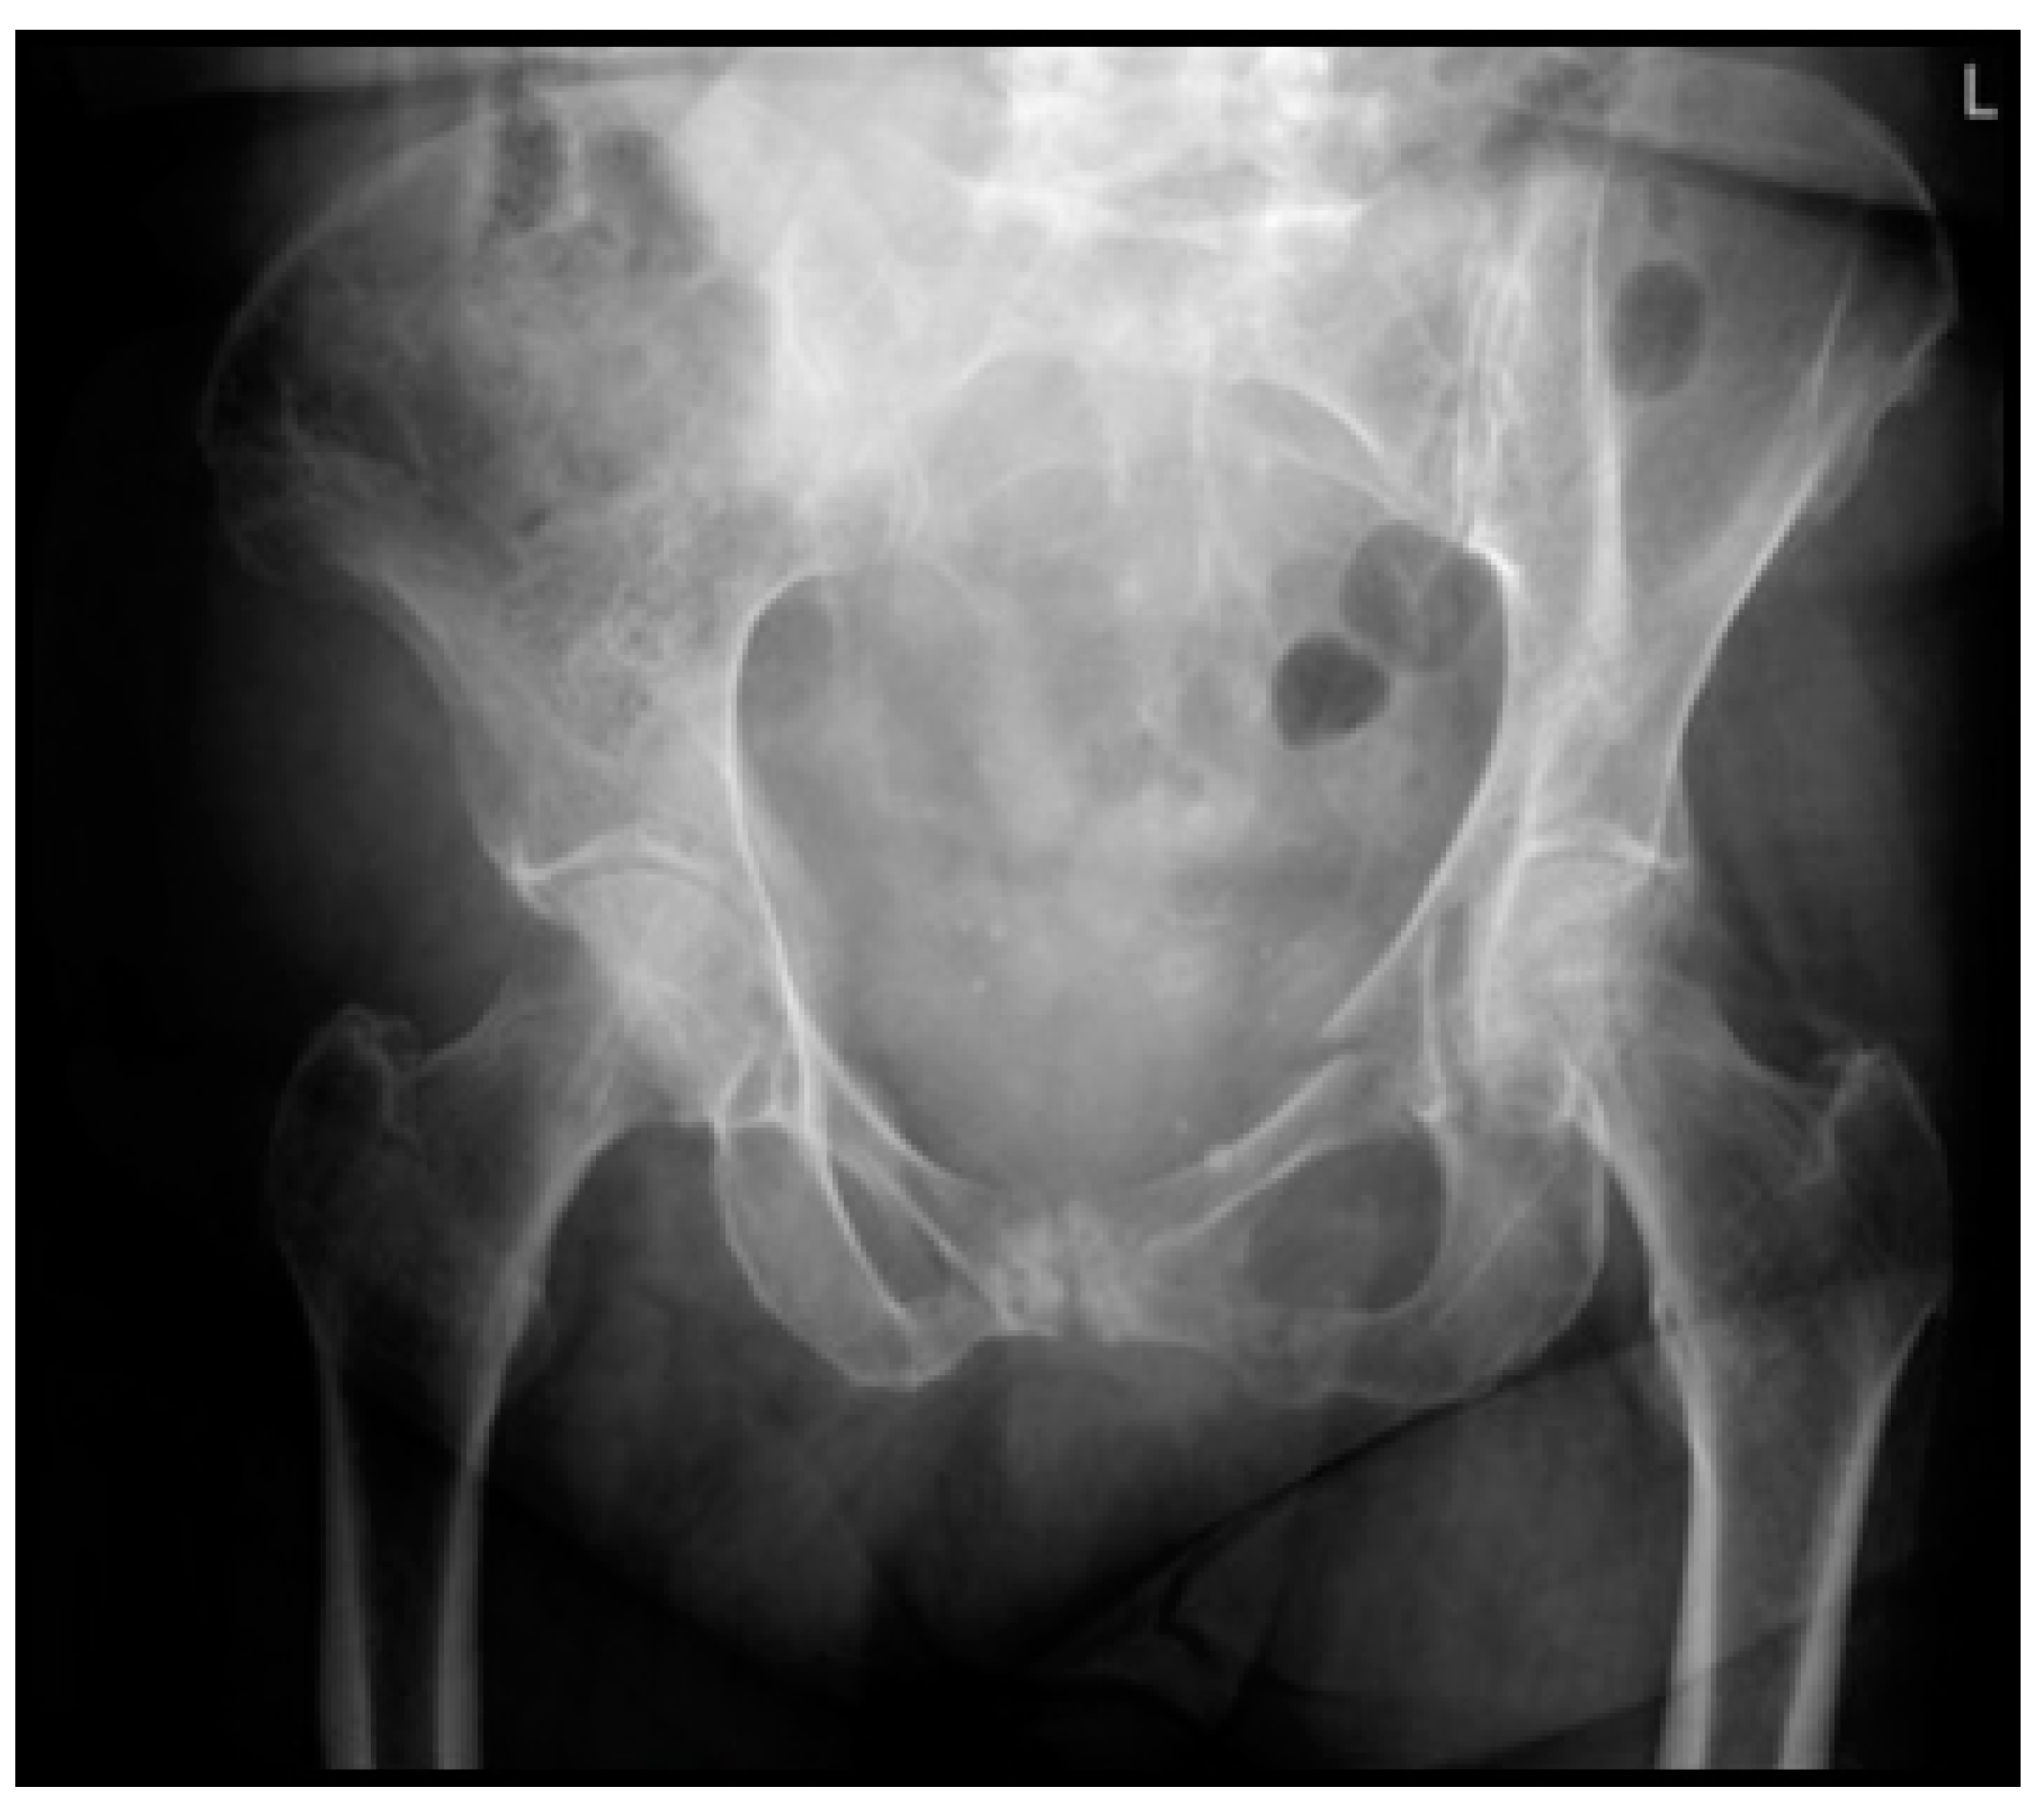

| 12. Mrs. A. is a 75-year-old, independently living ASA 2 patient. She tripped and fell at home. Plain radiographic imaging showed a superior/inferior ramus fracture on the left side. Would you, based on this information, perform a CT scan in the hospital you work at? | A. No, a CT scan has no treatment consequences B. Yes, always C. Yes, if the patient has pain on palpation of the sacrum D. Yes, if the patient is very painful during mobilization E. Otherwise, namely: |

| 13. Mrs. B. is a 77-year-old ASA 4 patient living in sheltered housing. She tripped and fell at home. Plain radiographic imaging showed a superior/inferior ramus fracture on the left side. Would you, based on this information, perform a CT scan in the hospital you work in? | A. No, a CT scan has no treatment consequences B. Yes, always C. Yes, if the patient has pain on palpation of the sacrum D. Yes, if the patient is very painful during mobilization E. Otherwise, namely: |